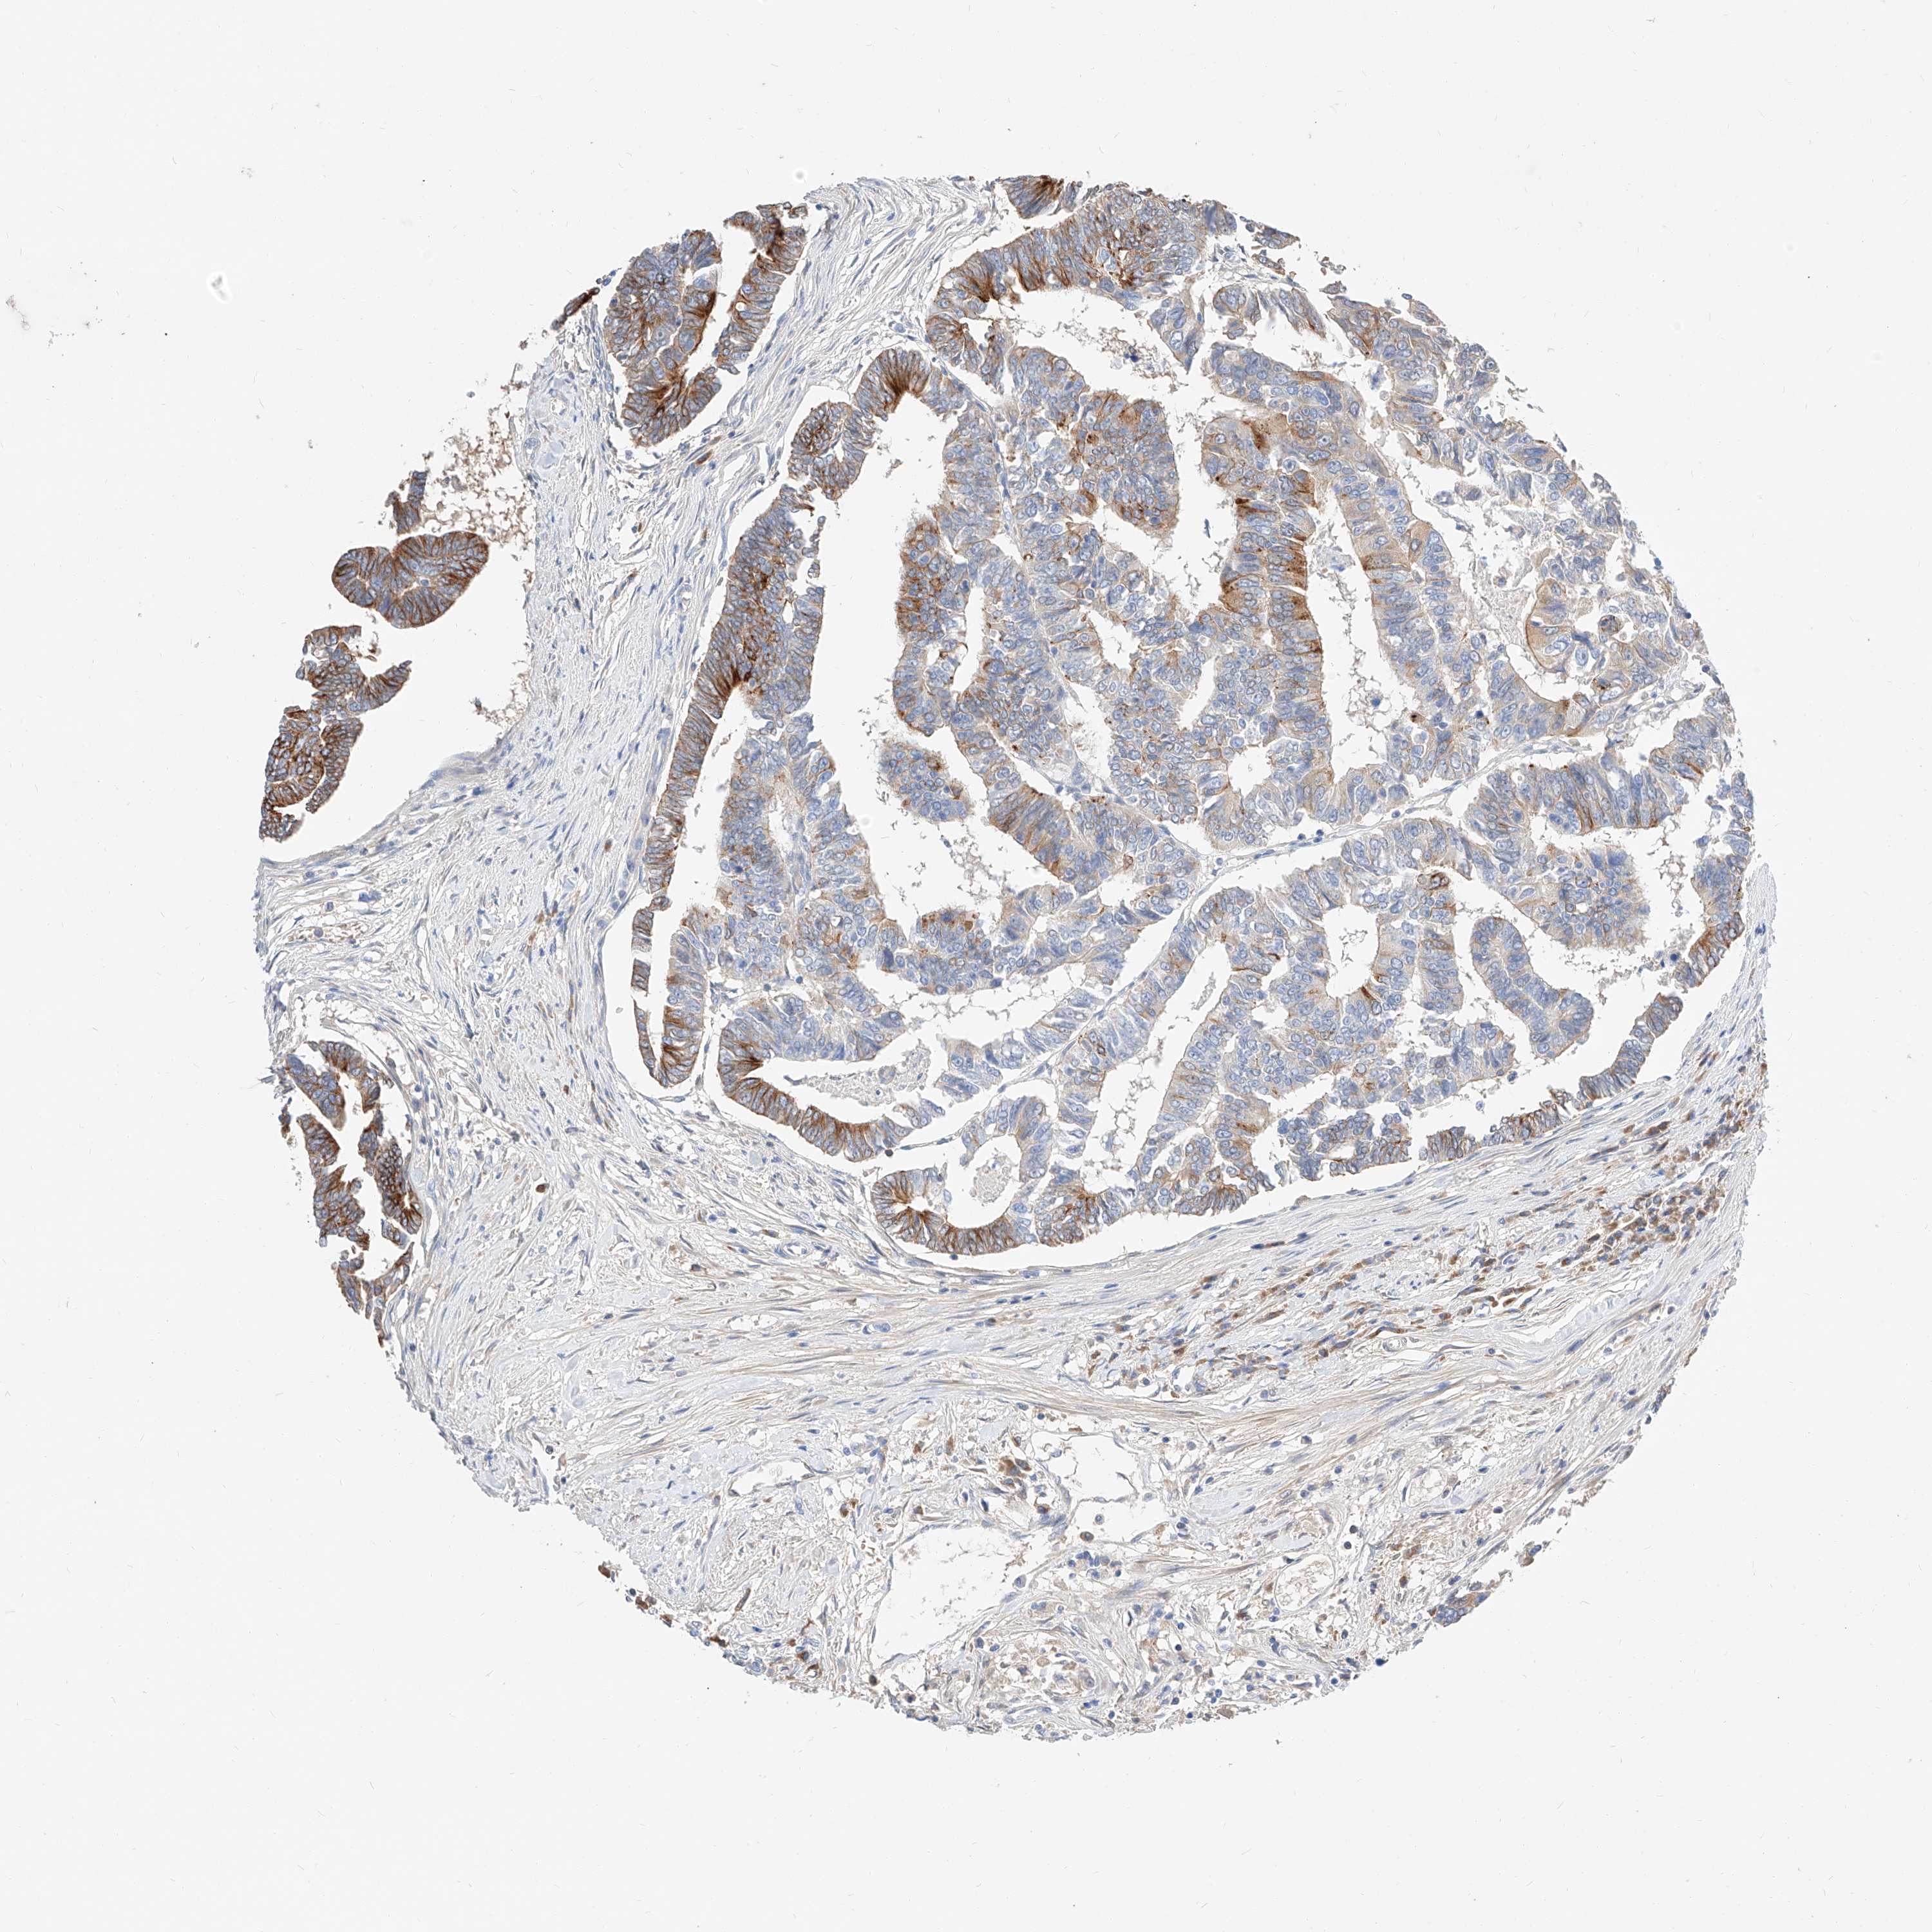

CANCER COLORECTAL CANCER Show tissue menu

COAD TCGA COAD VALIDATION READ TCGA READ VALIDATION PROTEIN COAD CPTAC PROTEIN EXPRESSION

ANTIBODIES

AND

VALIDATION